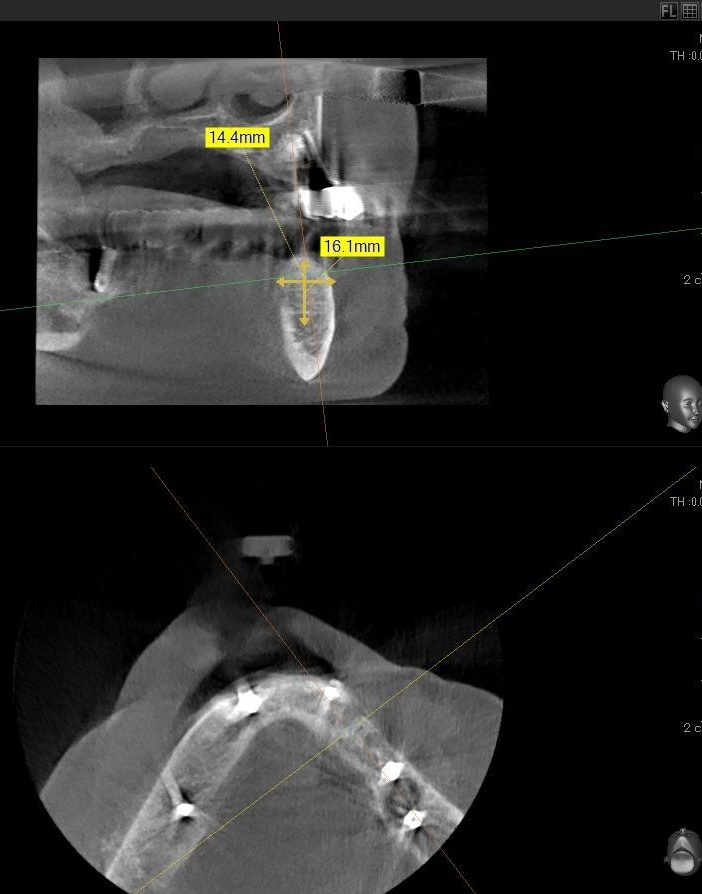

ドリルの先端を細い物から徐々に大きい物に変えながら、植立するインプラント体のネジの部分を除いた胴の部分の太さに合わせた大きさの穴を開けていきます。

開けた穴に、専用道具を使ってネジを締めるように長さ2センチ程のインプラントを骨に埋め込んでいきます。

しっかりとインプラント埋め込まれた後は、動揺がないか、噛んだ時に当たらないかなどを確認して、最後にパノラマ写真を撮影して今回のオペは終了となりました。